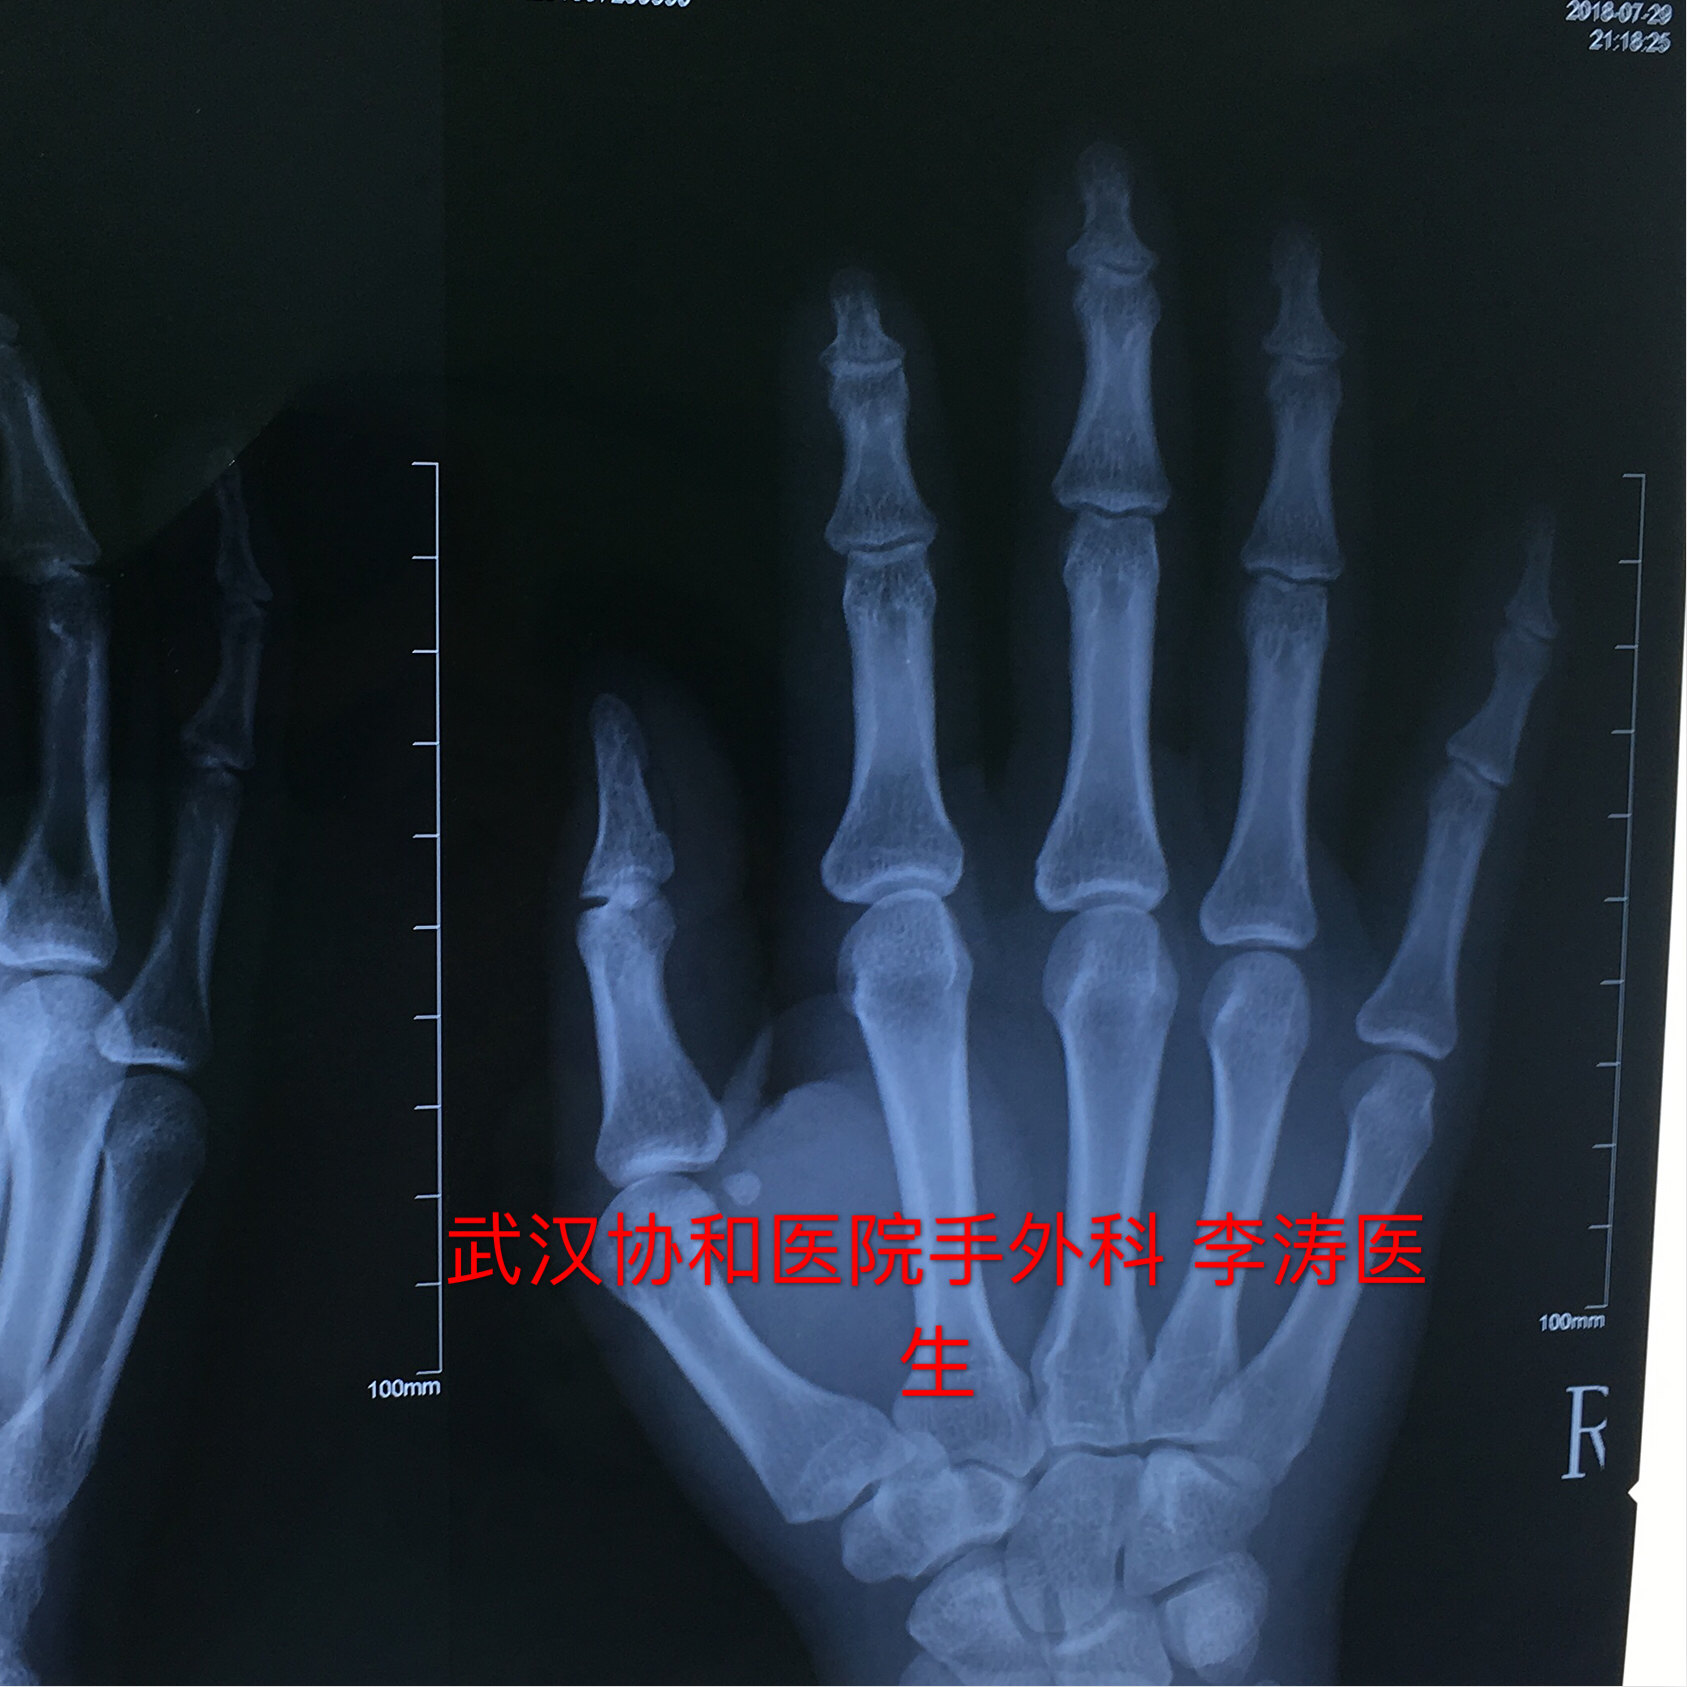

小指骨折手术-右手第五掌骨粉碎性骨折 第一个月张开手掌握拳训练 第二个月握力训练 捏网球 第三个月 感觉没什么了 就上单双杠了 附图一做完手术和三个月 —————————————————————— 这周去取了钢板,骨头上都是洞洞,同样的要恢复半年 术后一 平片提示:小指中节指骨颈部 3 型骨折。同样因闭合复位效果不满意改行手术治疗。具体过程如下。 图 2 小指指骨颈部骨折 3 型 a:正位片;b:侧位片 方法 先在透视下行闭合复位。行纵向牵引后将向背侧移位的指骨头向掌侧推挤(图 3),并保持骨折端复位。

平片提示:小指中节指骨颈部3型骨折。同样因闭合复位效果不满意改行手术治疗。具体过程如下。 图2 小指指骨颈部骨折3型。(a)正位片(b)侧位片 方法 先在透视下行闭合复位。行纵向牵引后将向背侧移位的指骨头向掌侧推挤(图3),并保持骨折端复位。你好,在战斗过程中,如果一侧手指骨折,打钢钉做手术,需要补偿精神损失和营养吗? 咨询时间: 1605 湖北 恩施州 交通事故 打架造成轻伤,小指骨折需要手术。被判刑需要多长时间 咨询时间: 湖北神农架林区劳动争议 我也要提问当前在线律师23,564位,如遇类似法律问题,立即咨询